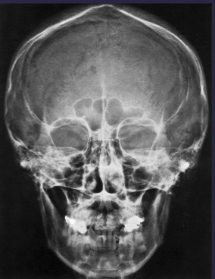

PA ceph is used to assess what

frontal + ethmoid sinuses

nasal fossa + orbits